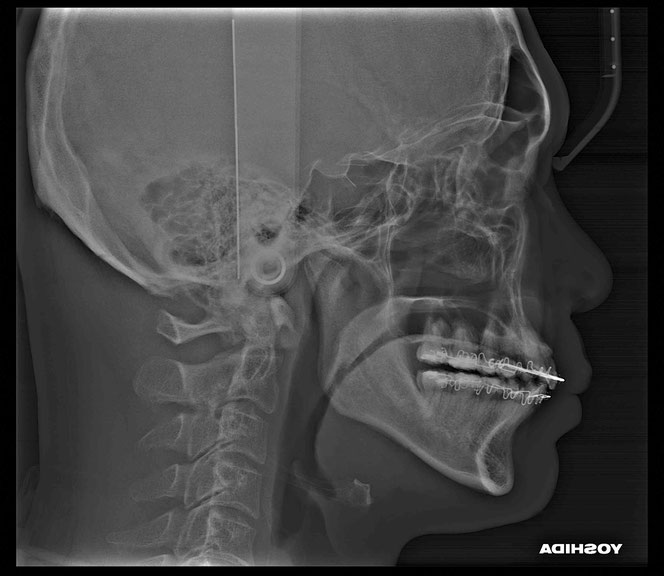

治療のポイントは“順番”

このような場合、

✔ 虫歯の除去

✔ 歯ぐきの再生治療

を組み合わせて行います。

単にレジン(白い詰め物)で埋めるだけでは、

再び虫歯になる可能性があります。